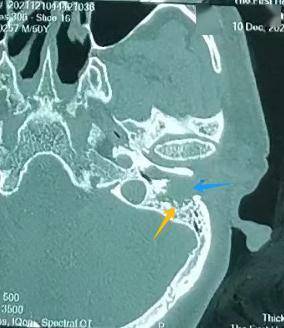

左耳:外耳道有肿物(左图) 对比右耳:外耳道通畅,鼓膜完整(右图)

张宏征发现,周先生左外耳道长了淡红色肿物,结合他长期的掏耳习惯,怀疑很可能是外耳道癌,立即为他进行外耳道肿物病理检查,结果证实周先生患的是罕见的"左外耳道鳞状细胞癌"。